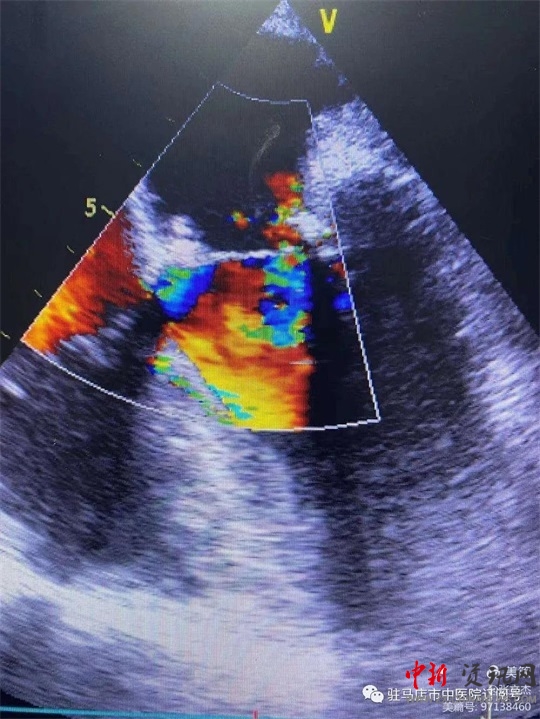

術(shù)前經(jīng)食道心臟超聲

復(fù)跳后經(jīng)食道心臟超聲,二尖瓣功能較術(shù)前明顯改善。